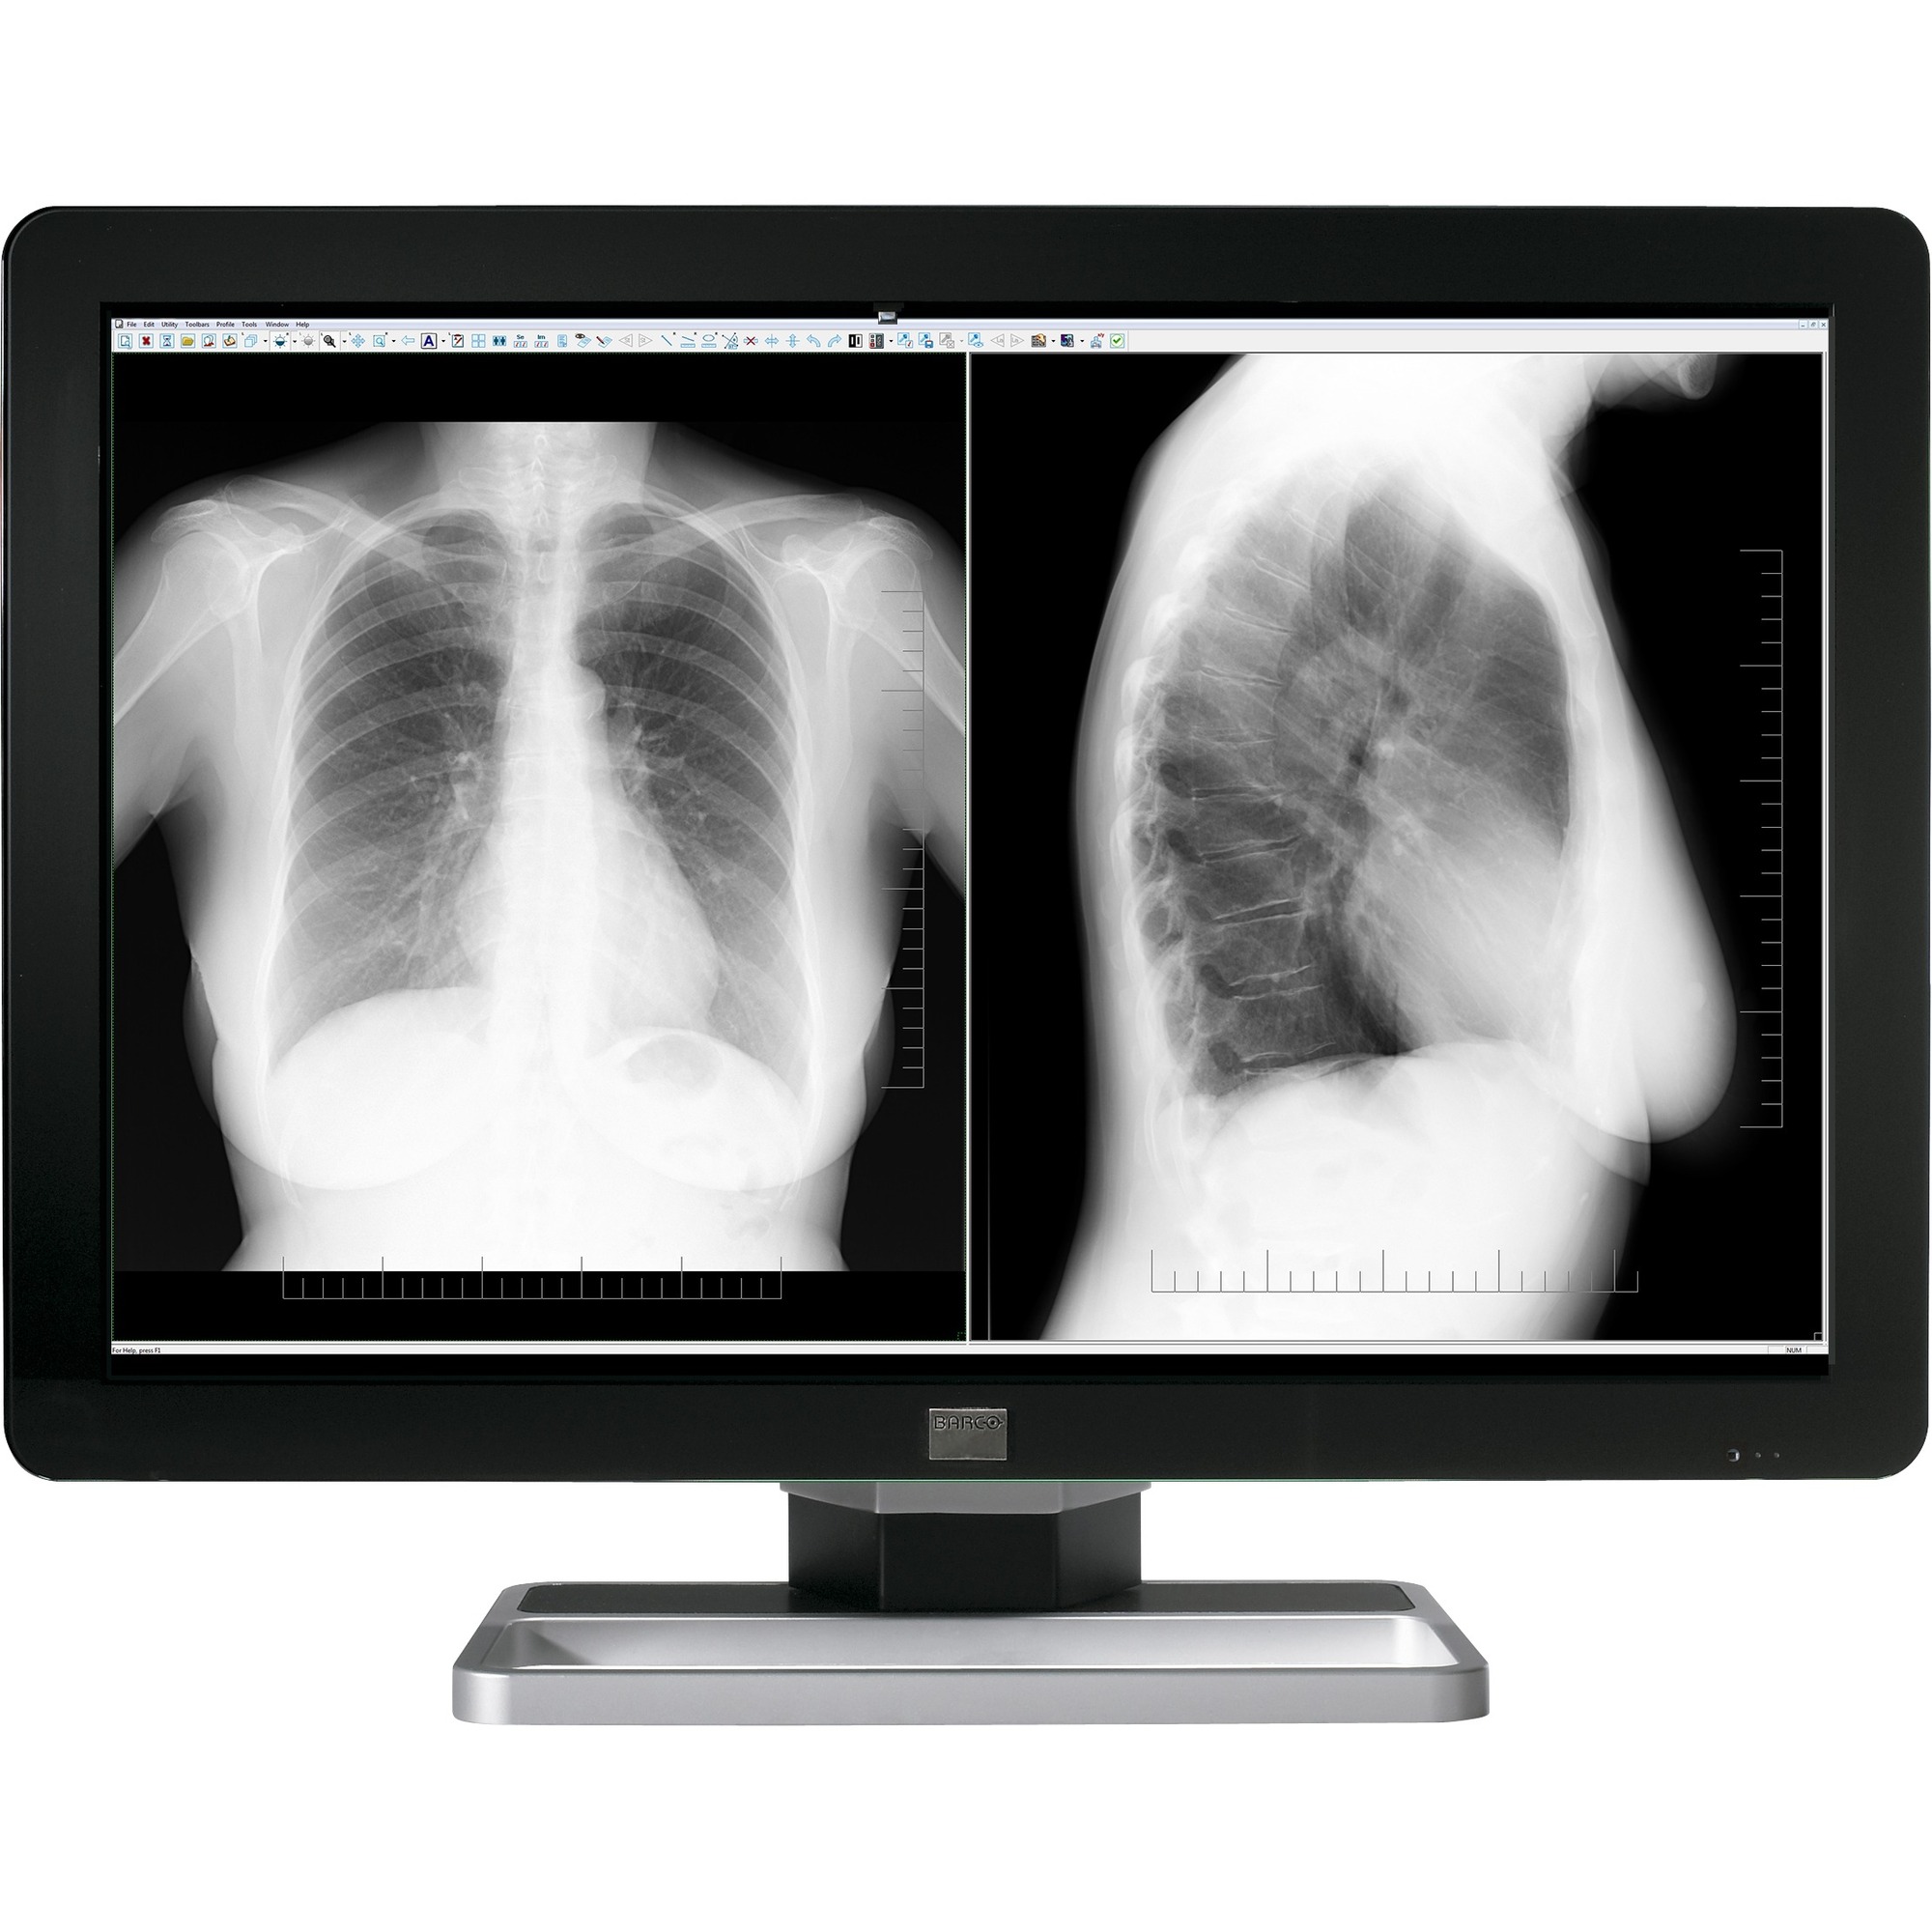

| A pleasure for your eyes Barco's Coronis Fusion 6MP features an exclusive LCD panel with the latest IPS technology, offering best-in-class image quality. Its high brightness and high contrast ratio help unveil the subtlest of details so you can make the most accurate diagnosis. Its large 30" screen real estate, wide aspect ratio, and full ACR compliance make this display the perfect fit for diagnostic imaging. Boost your productivity This display system comes with smart features that enhance control and productivity. Unique SpotViewTM technology allows you to boost the luminance in a region of interest while dimming the surrounding image area so you can focus on more details more efficiently. Like all of Barco's medical display systems, Coronis Fusion 6MP comes with MediCal QAWeb, a cloud-based technology for automated calibration and Quality Assurance to ensure maximum uptime of the display with no need for human intervention. Designed with ergonomics in mind With Coronis Fusion 6MP, switching between workstations becomes a thing of the past. Especially designed for multimodality imaging, this diagnostic display combines CT, MR, orthopedic images, or any other combination on a single screen - for an uninterrupted workflow. You can use the single-head workstation as two bezel-free heads or as one wide-screen workspace. The choice is yours. Its widescreen, ergonomic form factor, wide viewing angle, and DimViewTM feature (to automatically dim auxiliary displays) have been designed for the way you work and help you focus on the smallest image details. A one-stop-shop solution Barco medical displays include proprietary display controllers that are validated with the latest workstations and with all major PACS applications. All components are under the full 5-year warranty (including the display backlight) for complete peace of mind. |